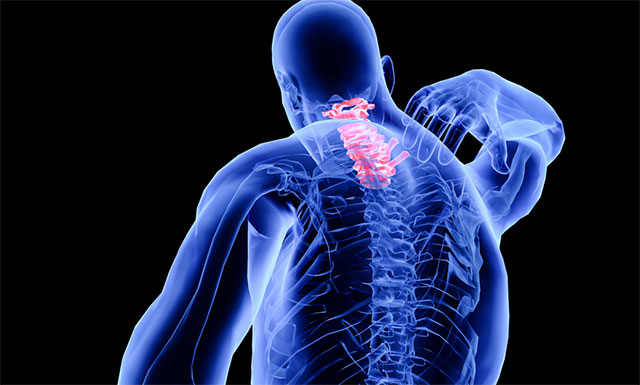

脊髓空洞癥是脊髓的一種慢性、進(jìn)行性的病變。其病變特點(diǎn)是脊髓(主要是灰質(zhì))內(nèi)形成管狀空腔以及膠質(zhì)(非神經(jīng)細(xì)胞)增生。常好發(fā)于頸部脊髓。當(dāng)病變累及延髓時(shí),則稱為延髓空洞癥。流行病學(xué)數(shù)據(jù)表明,該病每10萬人群中約2-8人發(fā)病,多見于20-50歲,女性多于男性,是一種比較少見的疾病。

▲ 脊髓空洞癥示意圖

上海藍(lán)十字腦科醫(yī)院神經(jīng)外科6A病區(qū)侯增欣主任介紹,脊柱是人體主要的支撐部位。脊柱內(nèi)部并不是實(shí)心的,而是由骨質(zhì)結(jié)構(gòu)圍成的空心“管道”,內(nèi)有脊髓和神經(jīng)走行,是腦組織向四肢和軀干傳遞的神經(jīng)通路,布滿神經(jīng)細(xì)胞和神經(jīng)組織。

脊髓空洞癥則是由于各種先天或后天因素導(dǎo)致產(chǎn)生進(jìn)行性脊髓病的脊髓空穴樣膨脹,臨床表現(xiàn)為節(jié)段性、分離性感覺障礙、節(jié)段性肌肉萎縮和傳導(dǎo)束性運(yùn)動(dòng)、感覺及局部營養(yǎng)障礙。脊髓空洞癥分為交通性和非交通性兩大類:交通性脊髓空洞癥意指空腔與脊髓中央管相通,是一種腦脊液通路的液體動(dòng)力學(xué)障礙疾病。反之,非交通性脊髓空洞癥只是脊髓內(nèi)的囊性擴(kuò)張,不與腦脊液通路相連。

脊髓空洞癥的病因可有先天性發(fā)育異常(如Chiari畸形)、腦脊液循環(huán)的機(jī)械性壓力改變和繼發(fā)于腫瘤、脊髓血管病后形成的脊髓積水等。小腦扁桃體下疝畸形(Chiari畸形)是引起脊髓空洞癥的常見原因。